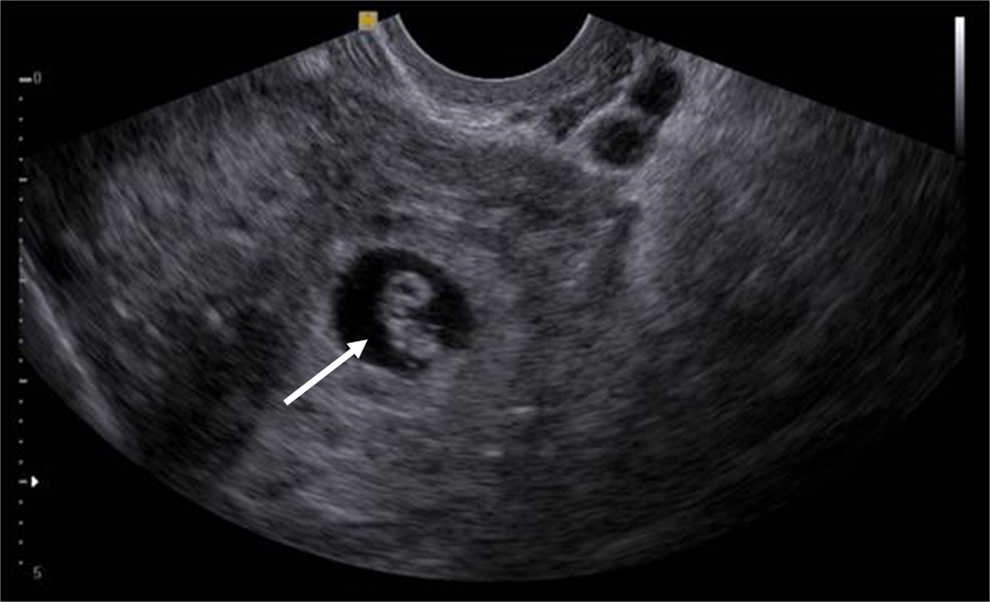

El signo del anillo tubario (tubal ring sign), descrito por primera vez por Timor-Tritsch y Rottem en el a??o 1987, corresponde a un hallazgo ecogr??fico observable en casos de embarazo ect??pico de localizaci??n tubaria1. Se define como una formaci??n anular hiperecog??nica (reacci??n trofobl??stica) que rodea al saco gestacional implantado fuera de la cavidad uterina (fig. 1). Su importancia radica en la alta especificidad y valor predictivo positivo para el diagn??stico de embarazo ect??pico tubario2.

Tipo I: estructuras embrionarias o extraembrionarias dentro de un anillo tubario bien definido. El embri??n puede detectarse con o sin latidos card??acos positivos (figs. 2 y 3).

La diferenciaci??n ecogr??fica puede realizarse tanto por v??a suprap??bica como endovaginal, siendo esta ??ltima la de elecci??n por su mayor resoluci??n imagenol??gica. Es importante determinar que la masa anexial es extraov??rica, ya que en la mayor??a de los casos la gestaci??n ect??pica se localiza en la porci??n ampular de la trompa. Con esta finalidad puede utilizarse el sliding sign, consistente en demostrar el libre movimiento entre el ovario y la masa, al realizar el estudio ultrasonogr??fico endocavitario combinado con una suave palpaci??n abdominal4,5.

Dentro de los tres tipos de anillo tubario descritos, el tipo I es el m??s frecuente (49,7%)4.